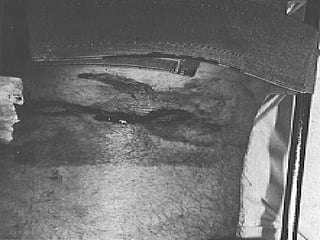

FRACTURA EXPUESTA Es la perdida de continuidad ósea, en  la que el foco de fractura se pone en contacto con el medio ambiente

PARAMETROS DE CLASIFICACION Medio ambiente en que sucedió Tiempo transcurrido entre la lesión y el tratamiento hospitalario El grado de lesión de las partes blandas del miembro afectado o áreas circunvecinas

CLASIFICACION DE LAS FRACTURAS EXPUESTAS Contaminadas : < de 6 hrs de evolución, contaminación por gérmenes del medio ambiente o el agente agresor Infectadas : > de 6 hrs de evolución, reproducción de los gérmenes localmente Complicadas : es la que se acompaña de lesiones en órganos, sistemas, o elementos anatómicos vecinos

FRACTURA EXPUESTA Esla perdida de continuidad ósea, en la que el foco de fractura se pone en contacto con el medio ambiente

PARAMETROS DE CLASIFICACIONMedio ambiente en que sucedió Tiempo transcurrido entre la lesión y el tratamiento hospitalario El grado de lesión de las partes blandas del miembro afectado o áreas circunvecinas

CLASIFICACION DE LASFRACTURAS EXPUESTAS Contaminadas : < de 6 hrs de evolución, contaminación por gérmenes del medio ambiente o el agente agresor Infectadas : > de 6 hrs de evolución, reproducción de los gérmenes localmente Complicadas : es la que se acompaña de lesiones en órganos, sistemas, o elementos anatómicos vecinos